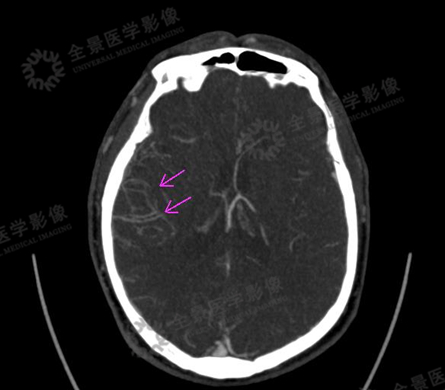

13岁男性患者,因头痛、头晕就诊。

CT平扫示:右枕叶散在钙化灶。

头颅灌注示:右枕叶异常灌注,CBF较左侧降低,MTT、TTD时间延长。